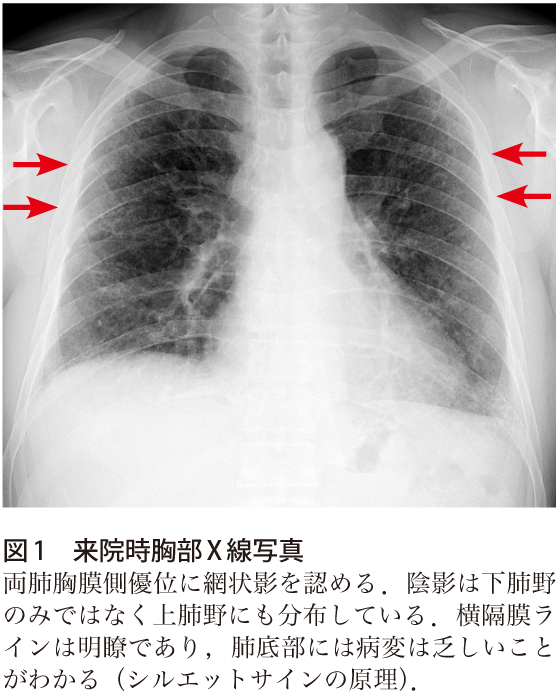

解答 解説 呼吸困難を訴える歳代女性 実践 画像診断q A 羊土社 レジデントノート 羊土社